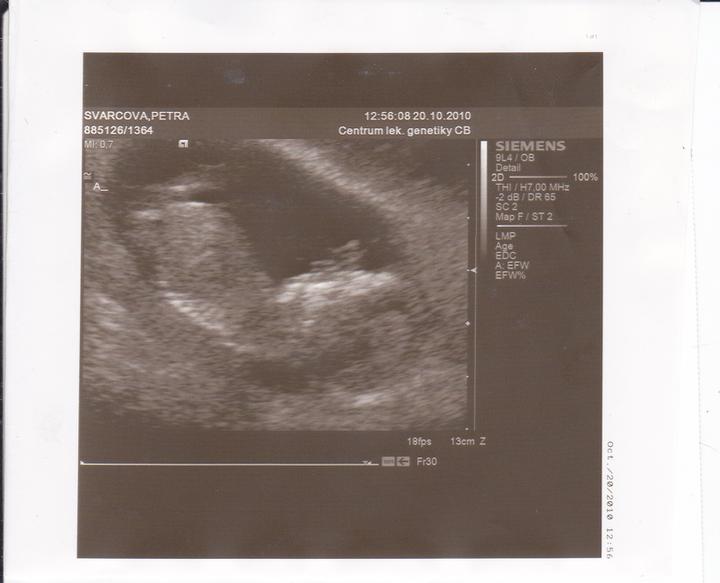

20.října-Dnes jsem byla v Českých Budějovicích na ultrazvuku.Obě mimi jsou v pořádku,jsou stejně velcí 6cm.Na ultrazvuku nebylo vidět pohlaví.